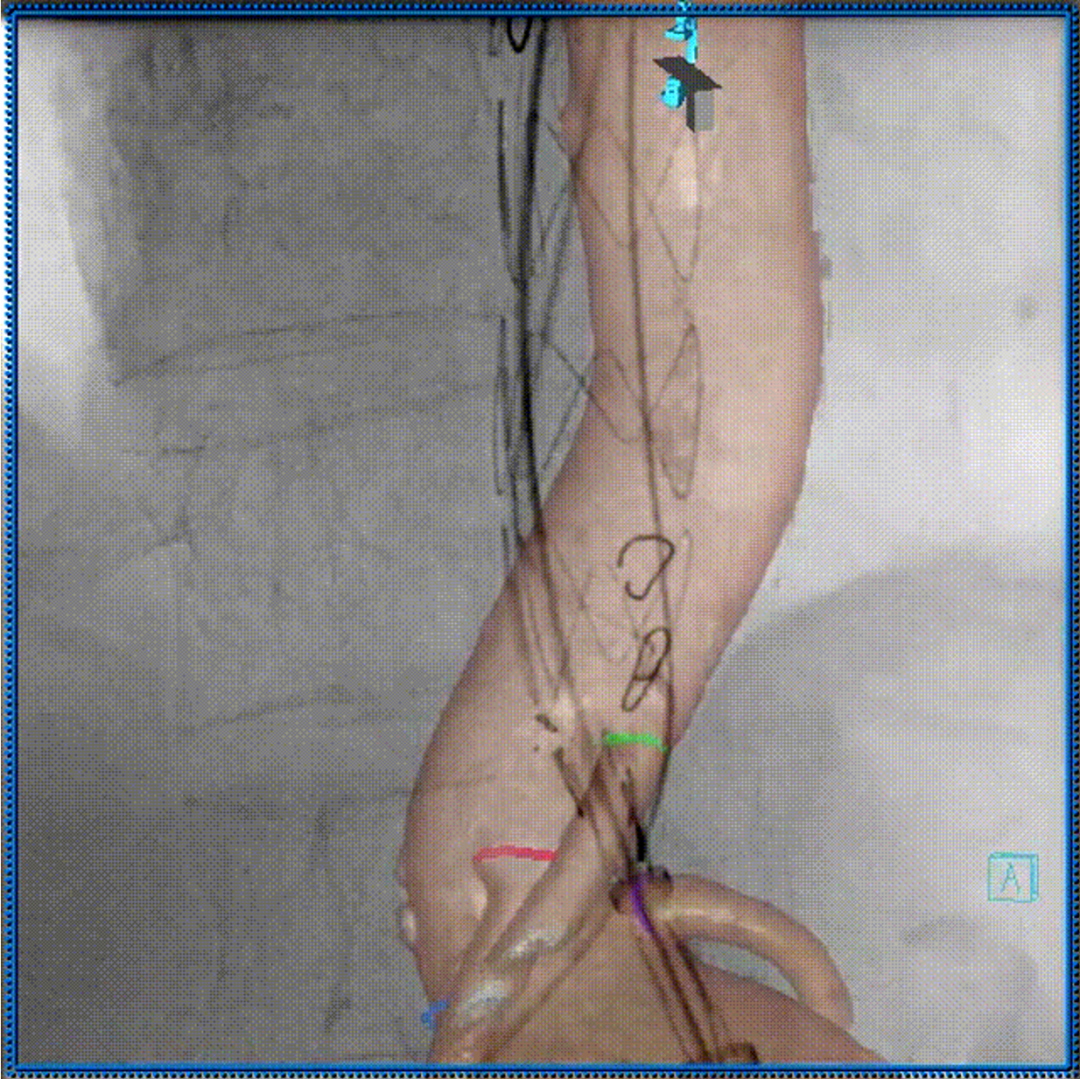

3D影像引导下完成窗口超选、置管及确认

肠系膜上动脉重建

左肾动脉重建

右肾动脉重建

四分支重建后造影,各分支血流通畅